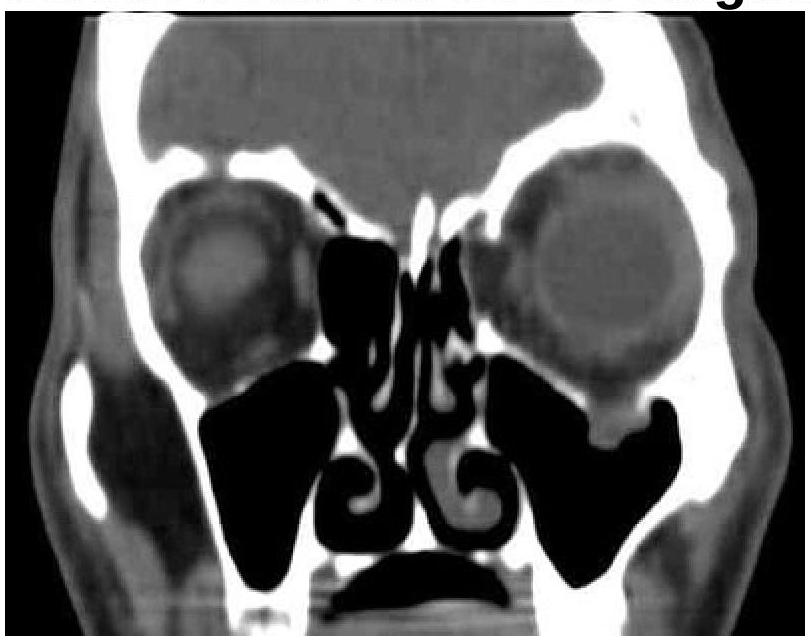

A patient presented with a history of diplopia and restricted eye movements. What is the most likely diagnosis based on the clinical and CT images?

Explanation: ***Blowout fracture*** - The CT image shows a **fracture of the orbital floor**, with associated **herniation of orbital contents** (fat and inferior rectus muscle) into the maxillary sinus. - This type of fracture commonly causes **diplopia** (due to muscle entrapment) and **restricted eye movements**. *Le Fort fracture* - Le Fort fractures involve the **midface and maxilla** as a whole, typically causing widespread facial instability. - They are classified into three types (I, II, III), none of which are exclusively characterized by an isolated orbital floor fracture with muscle entrapment. *Maxillary fracture* - While an orbital floor fracture involves the maxilla, a "maxillary fracture" is a broad term and does not specifically describe the characteristic features of **orbital content prolapse** and their resulting symptoms. - Isolated maxillary fractures might not cause diplopia or restricted eye movements unless they directly involve the orbit. *Zygomatic fracture* - A zygomatic fracture (either isolated or as part of a zygomaticomaxillary complex fracture) primarily affects the **cheekbone**. - While it can involve the orbital rim, it typically presents with **facial asymmetry**, **numbness** in the infraorbital nerve distribution, and sometimes **trismus**, rather than isolated muscle entrapment causing diplopia, as seen in the image.